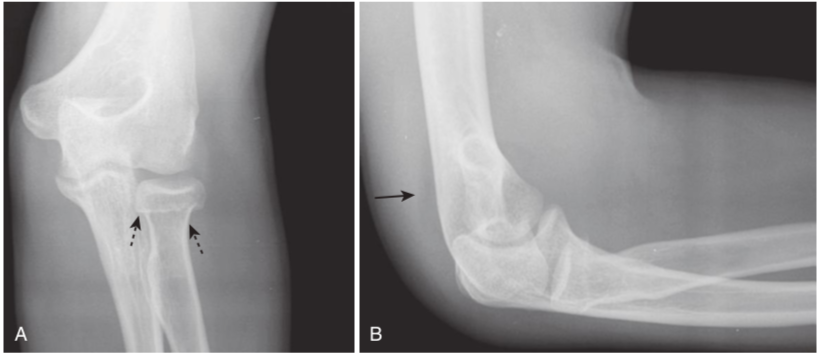

Fracture of radial head with joint effusion, frontal (A) and lateral (B) views.

A,Radial head fractures (dotted black arrows)are the most common fractures of the elbow in an adult. B,Look for fat density appearing as a crescentic lucency along the dorsal aspect of the distal humerus (solid black arrow)caused by intracapsular, extrasynovial fat that has lifted away from the bone by swelling of the joint capsule as a result of traumatic hemarthrosis—the positive posterior fat-pad sign. Virtually all studies of bones will include at least two views at 90° angles to each other called orthogonal views. Many protocols call for two additional oblique views, which enable you to visualize more of the cortex in profile.